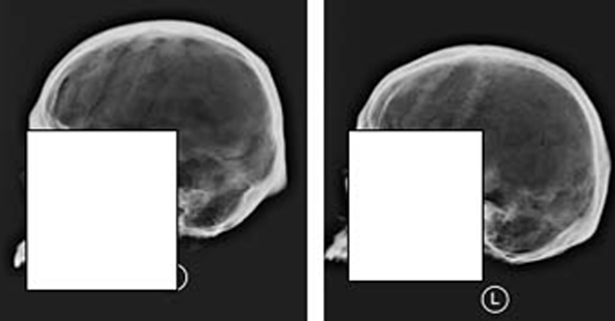

Specifically, only 56 percent of forensic anthropology Ph.D.s (the bone experts) could correctly match two images of the same skull, based solely on the “cranial vault outline” of the skull – the side profile of the skull running from just above the bridge of the nose to the point where the skull and neck meet.

下面,您将发现14个andemortem骷髅X射线和五个后骨折X射线。您需要将5次淘汰的X射线与适当的AnteMortem X射线匹配,有效地建立正面ID。让我们看看你是怎么做的!

第五个邮件X射线编号如下:1 =左上角,2 =左中心,3 =左下角,4 =右上角,5 =右下方。您可以单击图像以放大它们,答案位于帖子的底部。

后期X射线